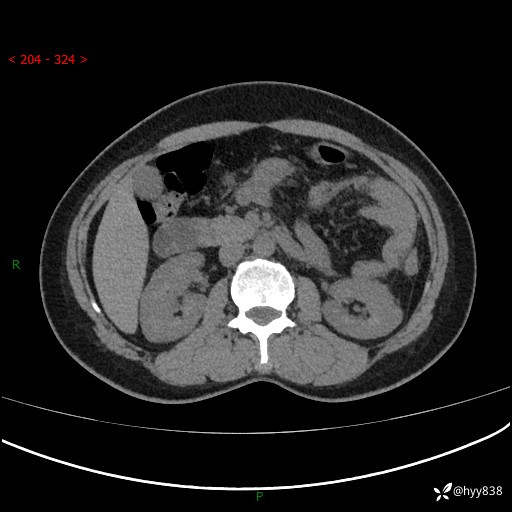

51岁/女,腹痛腹胀1天。白班偶遇,收藏教学备用---(公布详细手术过程)

现病史:患者1天前无明显诱因下出现左上腹部及腰背部胀痛不适,阵发性加剧,伴肛门停止排气;无发热,无恶心呕吐,无畏寒发热,无心慌气短等不适,于当地市第二人民医院就诊,行腹部ct检查提示左上腹区肠系膜血管从剧聚集,分布紊乱伴肠管局限性稍扩张积液,不完全性肠梗阻;考虑子宫颈纳氏囊肿,双侧附件区囊状灶;予以抗炎及对症支持等治疗后未见明显缓解,现患者为求进一步治疗来我院急诊就诊,遂以“肠梗阻”收住入院。 病来,神志清,精神可,饮食睡眠不佳,经灌肠后排便2次,小便正常,体力体重无明显变化。

上腹部CT平扫